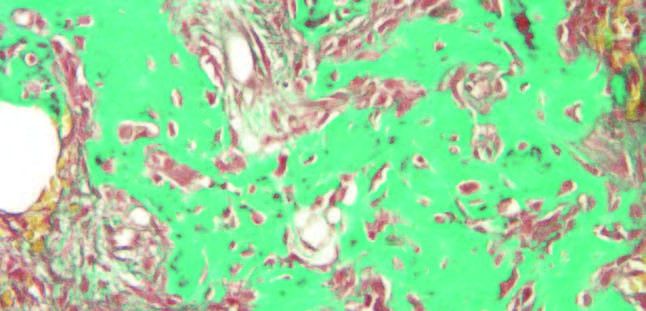

El análisis mediante tinciones de Hematoxilina-Eosina y Tricrómico de Masson, mostró una lesión fibro-ósea constituida por tejido conectivo fibroso con abundante celularidad fusiforme que rodeaba fragmentos trabeculares de tejido cemento-óseo vital con aposición celular blástica externa y clástica multinuclear, lo que confirma el diagnóstico de DCOF (Figuras 6 y 7).

La apariencia radiográfica de las lesiones suele mostrar correlación con las características histológicas. Los casos que presentan lesiones radiotransparentes con focos de opacificación o lesiones mixtas en la radiografía exhiben un tejido estromal abundante y celular, alta vascularidad y una cantidad baja a moderada de material mineralizado en forma de trabéculas cortas y curvilíneas. Por otro lado, las lesiones radiodensas disponen de una menor cantidad de tejido estromal con disminución de la celularidad, vascularidad mínima y láminas acelulares de material mineralizado13.